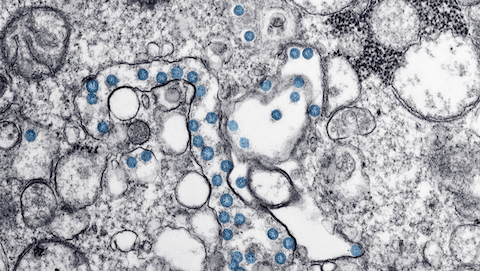

covid_page3

Published April 8, 2020 at 480 × 271 in Moyers & Company